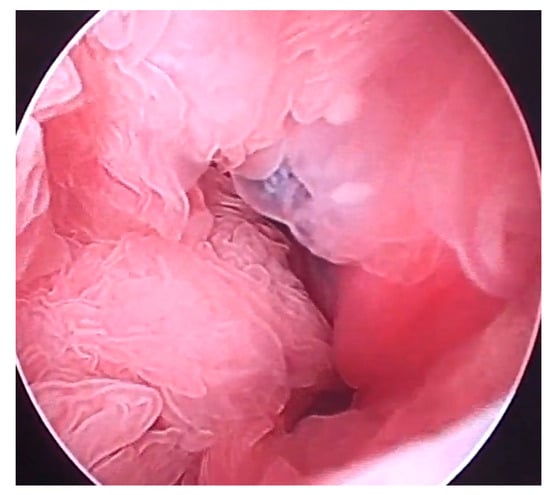

Hysteroscopy: Under the same anesthetic condition, the animal was subsequently examined by hysteroscopy using a gastroscope (Fujifilm EG 530NP; outer diameter 4.9 mm and working channel 2.0 mm, Fujifilm Co., Tokyo, Japan) and a video processor (TC200EN; KARL STORZ Endoscopy Japan K.K., Tokyo, Japan). Under endoscopic observation, while moving the introduced endoscope toward the deep areas of the uterine lumen, a large amount of clear fluid content without turbidity accumulation was seen within the uterine lumen. The corrugated thickening of the endometrium was observed throughout the uterine lumen (Figure 3). Water flushing from the endoscope into the uterine lumen appeared to float in the endometrial corrugations, suggesting softer structures. The endometrial surfaces were pale pink without discoloration. The corrugated structures were collected using biopsy forceps (2.0 mm × 1150 mm; Olympus FB-211D, Olympus Medical Systems Co., Tokyo, Japan) and introduced through a working channel.

Hysteroscopy is routinely used for intrauterine catheterization and artificial insemination in goats [27,40]. In the present case, hysteroscopy was performed under deep anesthesia for CT examination before the procedure. Hysteroscopy has been performed in previously examined bovine, buffalo, equine, and caprine cases in their standing position, with or without sedation [27,28,29,30,41]. Epidural anesthesia is required when hysteroscopy is performed in unanesthetized animals [27,28,29,30]. The applicable diameters of endoscopes to be introduced into the uterine lumen of examined goats have ranged from 5.0 to 5.5 mm [10,30]. The smaller diameter of an endoscope (e.g., 2 mm) may be recommended for application in female caprine cases, based on a previous practical record wherein the intrauterine introduction of the larger diameter of the endoscope was faulty in 55.8% of uteri if incision in the cervix was not made [10,40]. The intrauterine infusions of sterile saline or lactated Ringer’s solution can lead to the distention of the uterine lumen, contributing to good endoscopic observations [30]. Flushing of the uterine lumen was performed in the same manner as in the present case, allowing for the observation of color and turbidity of the intrauterine effusion and subsequent cytological and bacteriological examinations, although the stirred mucopurulent materials could cause unclearness in the hysteroscopic view in the previous cases [30]. Endometritis is a common uterine disease for which hysteroscopy is preferred [10,29,30]. The previous use of hysteroscopy in sick female goats enabled the identification of endometritis in 45.2% of cases, followed by the detection of endometrial hemorrhages, hydrometra, mucometra, and pyometra in 19.4, 16.1, 9.9, and 9.7% cases, respectively [10]. The common hysteroscopic appearances of endometritis are the discoloration and thickening of the endometrial walls of the affected uterus, whereas ultrasonography enables the demonstration of only endometrial thickening [10,26,29]. Additionally, the corrugation of thickened endometrial walls can be commonly identified in hysteroscopic observations [29], similar to that in the present case. Hysteroscopy-assisted biopsy was successfully performed to identify endometritis preoperatively in the present case. Thus, this technique is the most optimal approach for hysteroscopy, which has also been performed in previous caprine cases [9,27,28]. Under hysteroscopic observations, biopsy specimens can be selectively collected from the pathological surface of the endometrium, identified based on discoloration and ulceration, using pilling biopsy forceps [16,17,41]. The hysteroscopic detection of endometritis can consequently contribute to the diagnosis of hydrometra because these uterine lesions mostly occur concurrently in affected female goats [9,10].

Figure 3. Hysteroscopic appearance of the uterus. Corrugation is evident in the whole area of the endometrial walls.